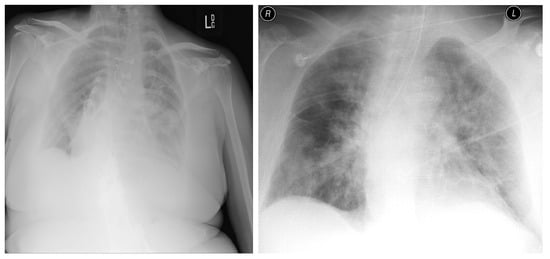

3.1. COVID-19 Image Data Collection (CIDC)

3.2. COVID-19 Radiography

3.3. BIMCV COVID19+

3.4. RSNA

3.5. Chest X-ray Images Pneumonia (CXRIP)

3.6. Montgomery County X-ray

3.7. Shenzhen Hospital X-ray

3.8. National Institute of Health (NIH)

3.9. Montfort Dataset